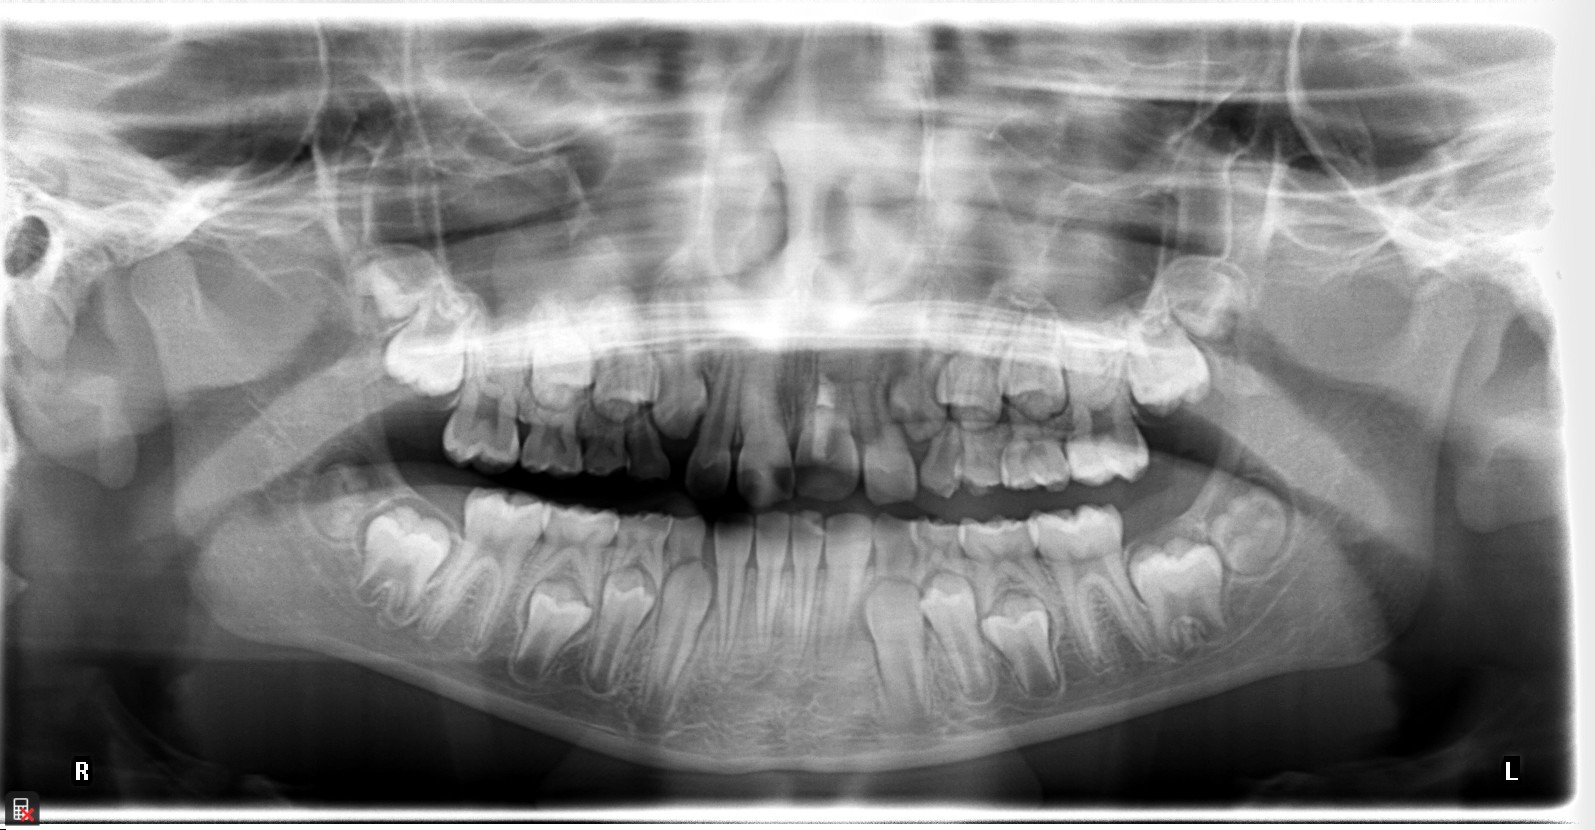

This is a 9yo girl with a high esthetic desire (wants to be a model/actor). She avulsed tooth #9 about 3 years ago, and she has been under treatment with other endodontists. I guess they attempted revascularization with MTA about year ago. #9 is ankylotic with a few mm’s infraposition. It is gray due to the MTA. #8 is slightly yellow/white due to calcification/obliteration but she says she feels cold testing and it is otherwise asymptomatic.